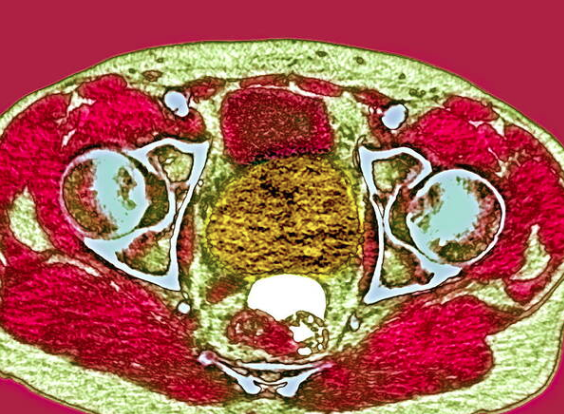

Figure 2. MRI prostate cancer. Axial couloured magnetic resonance imaging (MRI) scan of the pelvis of a patient with prostate cancer.